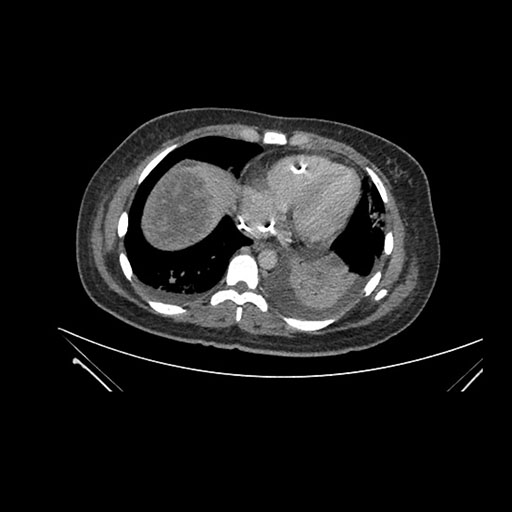

Axial Arterial